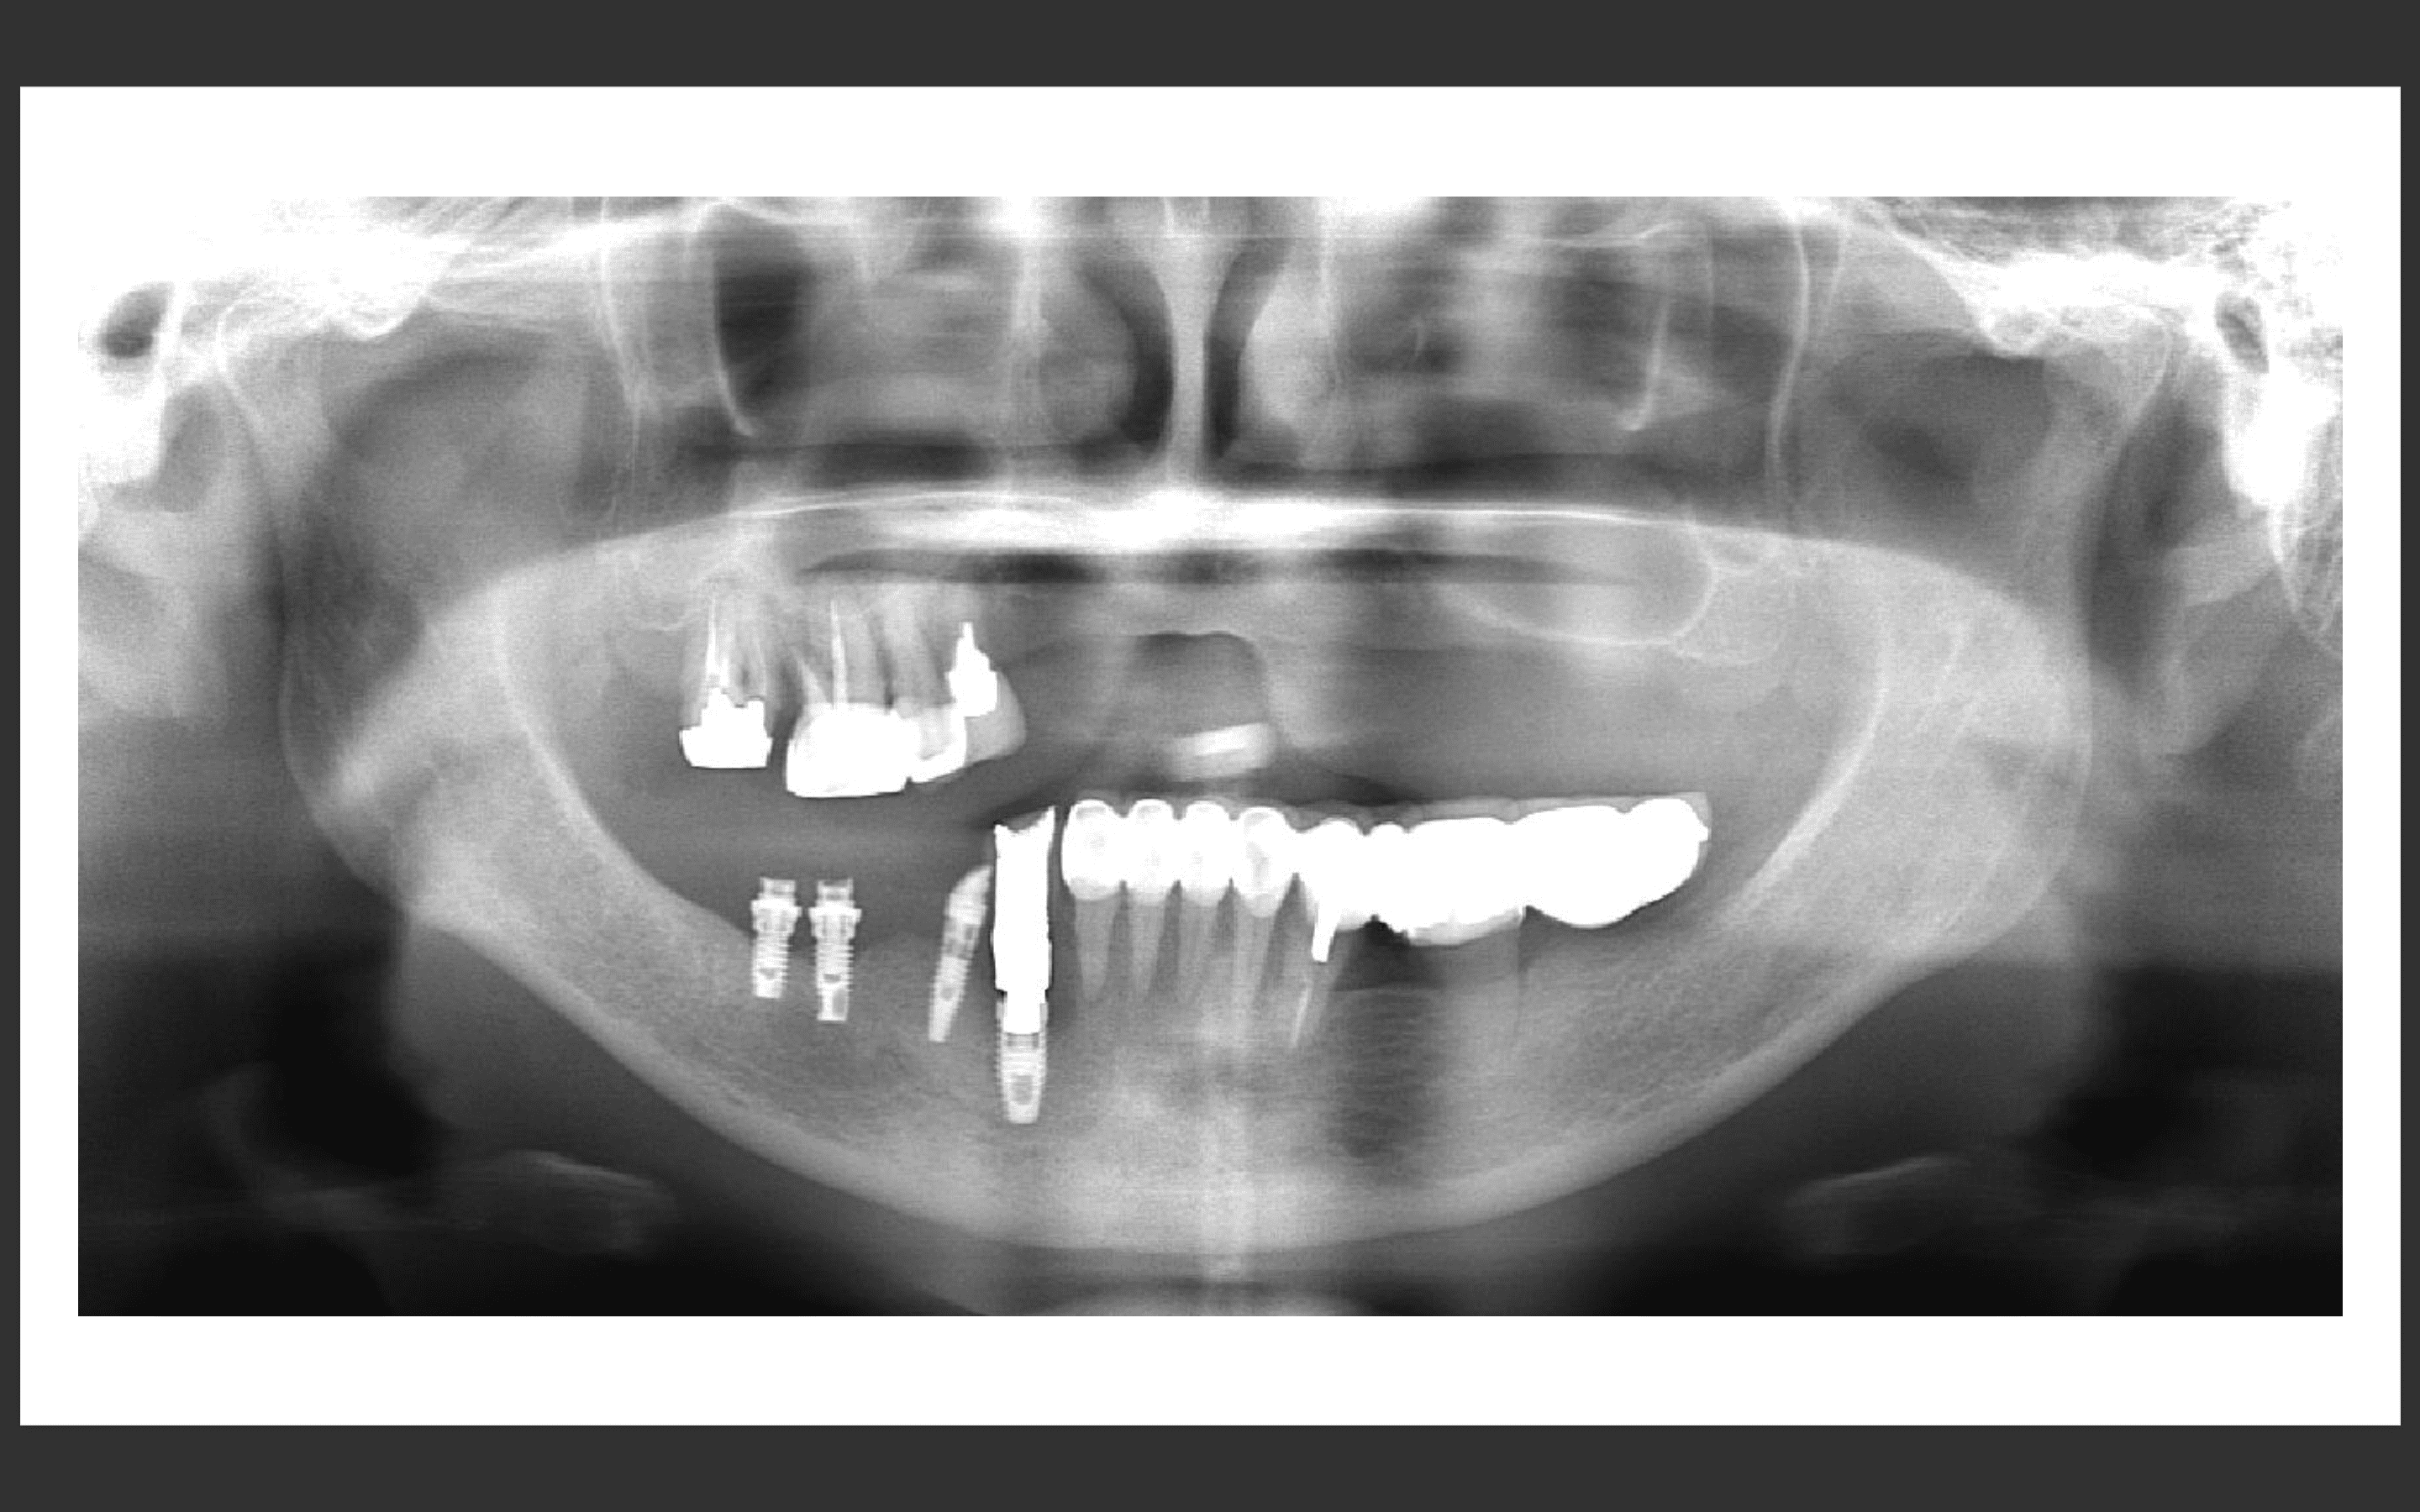

パノラマX線

上顎:インプラントは保存できる状態。

下顎:インプラントを含め全て保存不可能な状態。